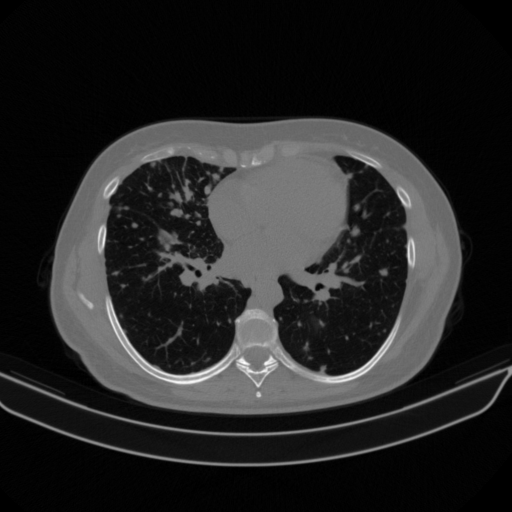

Targeted Slice 70 - Lung Window Analysis (Generated vs Real Venous)

0.752

Lung SSIM

110.9

Lung RMSE

46.5

Lung MAE

Average Lung Window Metrics Across All Slices (40 slices) - Generated vs Real Venous

0.745

Lung SSIM (Avg)

111.4

Lung RMSE (Avg)

45.4

Lung MAE (Avg)

Lung window (WL -600, WW 1500 β†’ Low βˆ’1350, High +150)

Original VENOUS CT scan